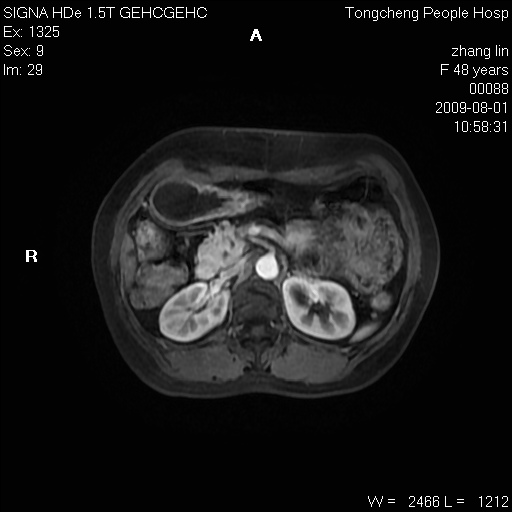

女,48岁。健康体检,彩超发现右肾占位性病变。平素健康。

临床诊断:右肾占位性病变,性质待定(囊肿?肿瘤?)。

上中腹部mr平扫+增强扫描,图像如下:

右肾上极见一类圆形病灶,t1wi呈等信号t2wi呈等高混杂信号,三期增强无强化,边界清---考虑囊肿出血。

同反相位均表现为等信号,病变无强化,考虑含蛋白的囊肿可能,弥散加权相或许有些帮助,

慢性胆囊炎